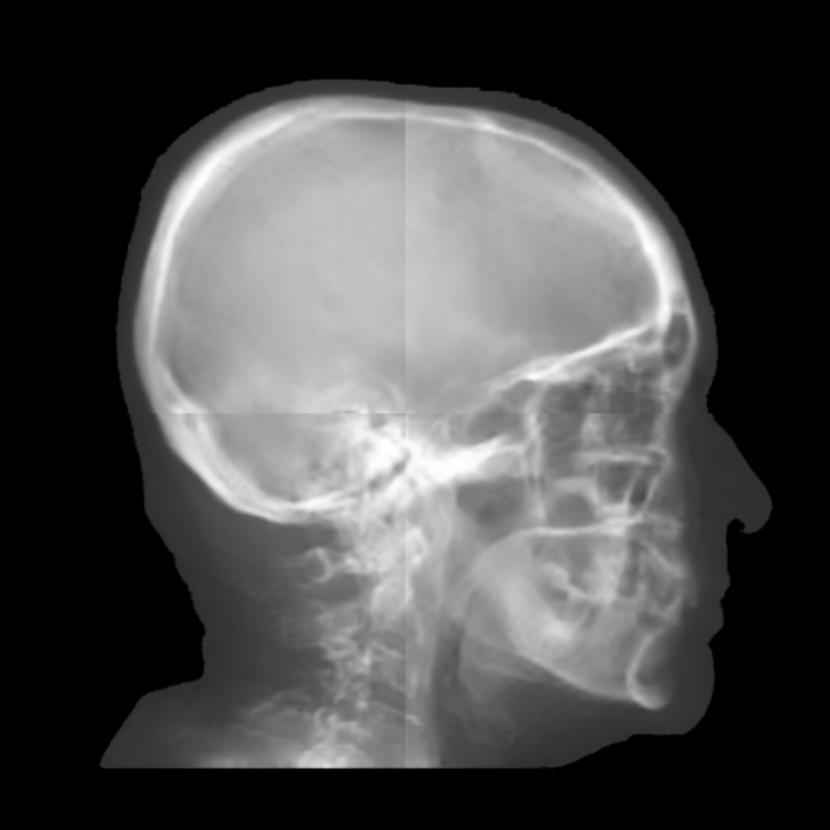

Refer to caption

(a) Real cephalogram

(b) Synthetic cephalogram

(c) Plot of samples and sigmoid curves

Fig. 2: Image contrast difference between real conventional cephalograms and RayCast synthetic cephalograms: (a) a real cephalogram example; (b) a RayCast synthetic cephalogram example; (c) the plot of samples between RayCast synthetic cephalograms and real cephalograms with an original sigmoid curve (red) and our proposed modified sigmoid curve (blue).

In Fig. 2, one real conventional cephalogram example and one example of 𝒈𝒈\boldsymbol{g} are displayed, where evident image contrast difference between these two images is observed. It is because the X-ray films used in conventional cephalograms have the special nonlinear optical property that the characteristic curve between optical density and logarithmized X-ray exposure has a sigmoid-like shape [42]. According to the Lambert-Beer law, the logarithmized X-ray exposure is equivalent to the attenuation integral. It indicates that the intensity relation between the desired cephalogram and the attenuation integral image 𝒈𝒈\boldsymbol{g} should also exhibit a sigmoid-like curve. Therefore, to make the image contrast of synthetic cephalograms similar to conventional cephalograms, a sigmoid intensity transform is necessary.

To find the parameters for the above general sigmoid transform, the mean intensity values of samples chosen in certain regions of 𝒈𝒈\boldsymbol{g} together with the corresponding values sampled from real conventional cephalograms are plotted as black dots in Fig. 2(c). The sigmoid transform of Eqn. (4) is plotted as the red-dotted curve, whose parameters are determined by least squares curve fitting. As displayed, most samples are located near the sigmoid curve, which is consistent with the characteristic curve in X-ray films. Note that the positions of the samples are approximated very coarsely due to the absence of dental CBCT volumes and their corresponding cephalograms. With matching pairs, a more accurate intensity transform can be learned.

where the intensity transform is a modified sigmoid function, illustrated as the blue-dotted curve in Fig. 2.